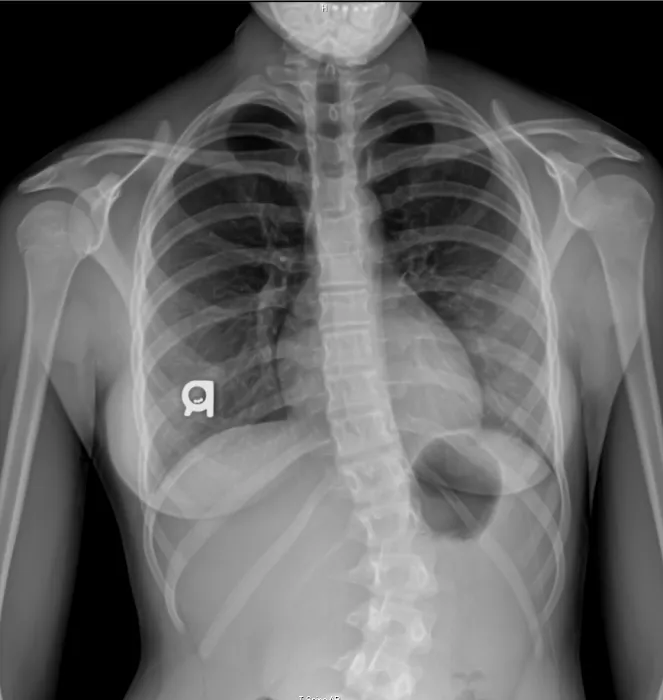

Dr. Lawrence Wood offers a wide array of services designed to address a variety of health concerns with a comprehensive and tailored approach. Public reviews highlight his ability to perform a thorough assessment, which includes utilizing tools like X-rays and computer software analysis to get a complete picture of a patient's spinal condition. This meticulous approach ensures that the treatment plan is not a one-size-fits-all solution but a personalized strategy for effective relief and long-term wellness. His services are not limited to in-office adjustments; a key component of his practice is patient education and at-home exercises. He instructs patients on the "best exercises to help you alleviate the pain and build up your strength in the necessary targeted areas," a feature that is highly valued by his clients. For residents of Brodheadsville and the Poconos, this means receiving care that is both proactive and preventative. Dr. Wood's commitment to educating his patients empowers them to take an active role in their recovery, leading to more sustainable results and a reduced reliance on continuous treatment. His ability to address and eliminate specific issues, such as thoracic numbness and hand numbness, as mentioned by a happy patient, speaks to his expertise and effectiveness. His services are a blend of hands-on therapy and empowering guidance, which makes his practice a trusted local resource.

- Comprehensive Spinal Assessment: Dr. Wood utilizes advanced diagnostics, including X-ray and computer software analysis, to get a precise understanding of a patient's spinal condition.